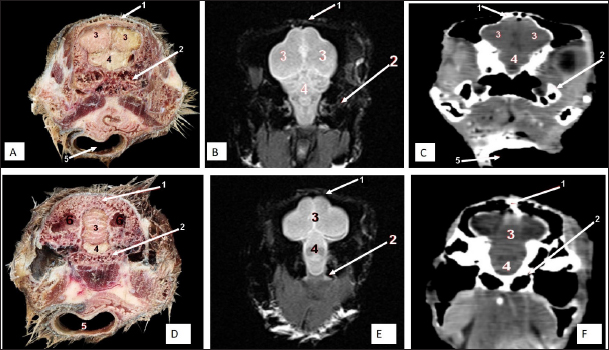

Fig. 9. Rostral-caudal cross sections of the adult ostrich head—level 4. Rostral views of A) photograph of an anatomical cross section, B) MRI and C) computed tomography images showing: 1- Os frontalis, 2- Frontal sinus, 3- Processus quadratojugale, 4- Eye ball, 5- Pars verticalis ethmoidale, 6- Infra orbital sinus, 7- Vomer, 8- Tracheal lumen surrounded by tracheal cartilaginous rings, 9- Sagittal eminence (wulst) of the cerebrum. Caudal views of D) an anatomical cross section, E) MRI and F) computed tomography images showing: 1- Os frontalis, 2- Processus. quadratojugale, 3- Vomer, 4- Eye ball, 5- Infra orbital sinus, 6- Trachea, 7- Cerebral hemispheres of the brain.

Fig. 10. Rostral-caudal cross sections of the adult ostrich head—level 5. Rostral view of A) photograph of an anatomical cross section, B) MRI and C) computed tomography images showing: 1- Os parietale, 2- Os basisphenoidale, 3- Cerebral hemispheres, 4- Mid brain, 5- Trachea Plate. Caudal views of D) an anatomical section, E) MRI and F) computed tomography images showing: 1- Os parietale, 2- Os basioccipitale, 3- Cerebellum, 4- Pons, 5- Trachea, 6- Os temporalis.

The brain was divided into three parts: the hindbrain (medulla oblongata and cerebellum), the midbrain (cerebrum’s peduncles and optic lobes), and the forebrain (thalamus, pineal body, hypophysis, optic tracts, and chiasm, cerebral hemispheres, and olfactory lobes) (Figs. 2, 9, and 10). The sagittal section of the brain includes the olfactory bulb, cerebrum, cerebellum, medulla oblongata, optic lobe, optic chiasm, and hypophysis (Fig. 2). The dorsal median longitudinal fissure separates the cerebrum into two hemispheres. The sagittal prominence (west) was present on both sides of this fissure (Figs. 9 and 10).

The CT pictures revealed the skull as a readily discernible white structure due to its high CT density, while the brain appeared as a grey structure due to its intermediate density. However, the settings utilized made it impossible to identify different areas of the brain in the CT scans (Figs. 9 and 10C, F). The MRI pictures showed the brain as a whitish structure with a high signal intensity. This technique was used to identify various brain structures, including the hindbrain (medulla oblongata, and cerebellum), the midbrain (peduncles of the cerebrum, optic lobes), and the forebrain (thalamus, pineal body, hypophysis, optic tracts and chiasm, cerebral hemispheres, and olfactory lobes) (Figs. 2B, 9 E, and 10E). Additionally, the olfactory bulb, cerebrum, cerebellum, medulla oblongata, optic lobe, optic chiasm, thalamus, and hypophysis.